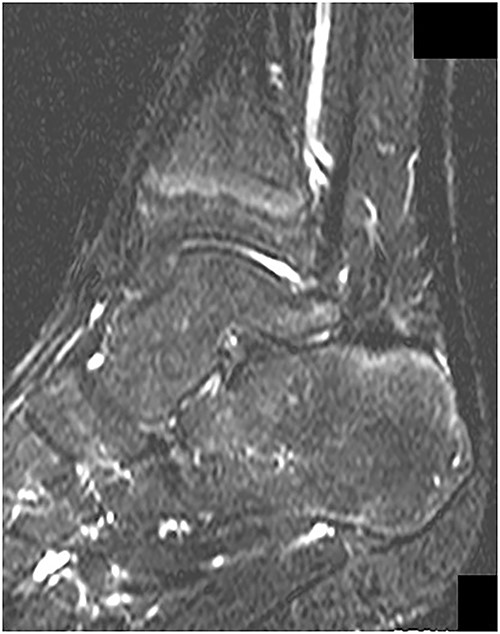

A 14-year-old male soccer player who belonged to a junior high school soccer club complained of right heel pain without trauma histories when he was playing a soccer. He had no medical history. He visited a local clinic and was treated with conservative treatment including rest, a non-weightbearing splint and anti-inflammatory medication for 4 days. However, his symptoms got worse, and so he visited our hospital. At the first visit to our hospital, physical examination revealed redness, local heat, swelling and tenderness around the insertion of the Achilles tendon. Also, his right foot was in equinus position, and it was difficult to correct his foot position accurate due to his heel pain (Fig. 1). Plain radiographs showed no abnormal findings (Fig. 2). Magnetic resonance imaging (MRI) demonstrated a low intensity signal on T1-weighted images and a high intensity signal on T2-weighted images in the retrocalcaneal bursa (Fig. 3). Laboratory examination revealed 2.1 mg/dL of C-reactive protein and 7.5 cells × 103/μL of white blood cell count. In addition, ultrasound-guided needle aspiration of the retrocalcaneal bursa resulted in 3 ml of purulent material and in which was positive for methicillin-susceptible Staphylococcus aureus (MSSA). We diagnosed him with septic RB caused by MSSA and started to treat with conservative treatment including a non-weightbearing splint and intravenous antibiotics therapy using cefazolin (6000 mg per day). However, his symptoms and laboratory results did not improve at 4 days after starting intravenous antibiotics therapy, and so we applied hindfoot endoscopic bursectomy for him.

MRI demonstrated a low intensity signal (arrow) on (A) T1-weighted images and a high intensity signal (arrow) on (B) T2-weighted images in the retrocalcaneal bursa.

MRI revealed no abnormal signs on short TI inversion recovery images at 1 year postoperatively.